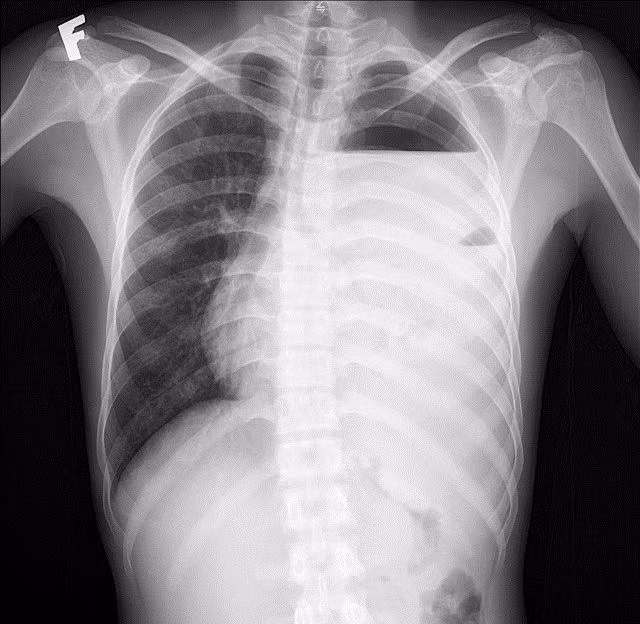

Hình ảnh phổi tổn thương trên phim chụp - Ảnh BVCC

Kết quả xét nghiệm máu cho thấy tình trạng nhiễm trùng nặng với chỉ số bạch cầu (WBC) lên tới 64.8 G/L, chỉ số CRP cao 263.6 mg/dL. Với hệ thống chẩn đoán hình ảnh hiện đại, các bác sĩ ghi nhận: Đông đặc nhu mô thùy dưới phổi trái, tràn dịch màng phổi trái lượng nhiều, tràn khí màng phổi trái, phổi trái bị xẹp thụ động, đẩy lệch trung thất sang phải.